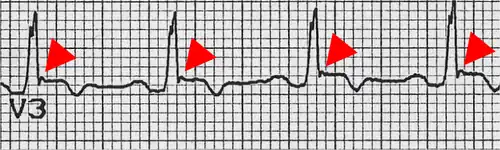

In der ursprünglichen rein "rechtsventrikulären" Form wurde beschrieben, dass mit dem Fortschreiten der Erkrankung immer mehr Muskulatur der rechten Herzkammer durch Fettgewebe ersetzt wird, wodurch sich die rechte Herzkammer vergrößert. Selten finden sich Einschränkungen in der Pumpfunktion des Herzens. Häufiger ist der bei körperlicher Belastung, wie beispielsweise Leistungssport, ausgelöste plötzliche Herztod (PHT) oder „Beinahe“-PHT, insbesondere bei jungen Menschen. Die Diagnose kann mittels Echokardiografie, MRT, EKG und McKenna-Score gestellt werden. Zur Behandlung kann ein Kardioverter-Defibrillator implantiert werden. Sportliche Belastungen sollten vermieden werden. Eine Herztransplantation ist in vielen fortgeschrittenen Fällen die Ultima Ratio.

Die ACM kann in jedem Alter symptomatisch werden, meist wird sie im jungen Erwachsenenalter manifest. Typische Symptome sind die der venrtikulären Arrhythmie oder der ventrikulären Fehlfunktion. Oft sind die kardialen "Biomarker" im Blut normal. Die Diagnose ist oft schwierig zu stellen und erfolgt oft aufgrund mehrerer hinweisender Auffälligkeiten in der Ventrikelfunktion, im histopathologischen Befund von Biospien, in typischen EKG-Veränderungen und in der ventrikulären Arrhythmie.

Allerdings kann es durch eine stärkere sportliche Belastung, einen Virusinfekt oder einen anderen externen "Trigger" zu einer "hot phase" kommen, die einem Akuten Koronarsyndrom, sogar einem Herzinfarkt, oder einer Myokarditis ähnlich sein kann, mit ST-Hebungen im EKG, aber ohne Stenosen der Herzkranzgefäße in der Koronarangiographie. In Biopsien lassen sich dann entzündliche Myokard-Infiltrate feststellen. Allerdings wird die Diagnose zunehmend ohne Biopsie, aber mit einer Magnetresonanztomographie des Herzens gesichert, bei der in bis zu 50 % der Patienten in der "hot phase" ein Myokard-Ödem und eine Spätanreicherung von Gadolinium zu finden sind.[4]

Brugada-Syndrom

Als klinische Entität ist das Brugada-Syndrom seit 1992 bekannt, es wird nach den beiden erstbeschreibenden Brüdern Pedro und Josep Brugada gelegentlich auch Brugada-Brugada-Syndrom genannt.[9] Manchmal ist es für den plötzlichen Herztod vor allem junger Menschen verantwortlich. Charakteristisch sind rechtsschenkelblockähnliche Veränderungen im EKG, die gegebenenfalls durch einen Ajmalin-Test provoziert werden können. Verschiedene Gendefekte sind bekannt, sie wurden von Ramon Brugada, dem jüngsten der drei Brugada-Brüder, beschrieben.